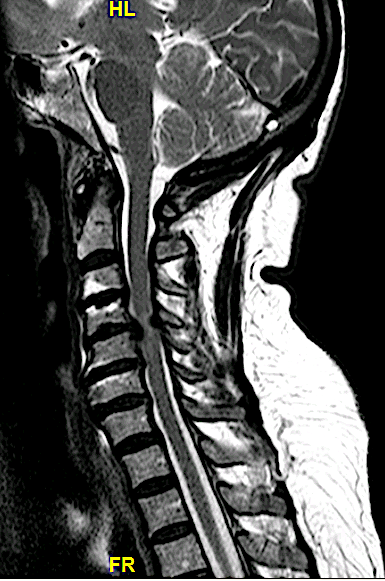

Obsérvese la compresión anterior y posterior (por el «pliegue del ligamento»